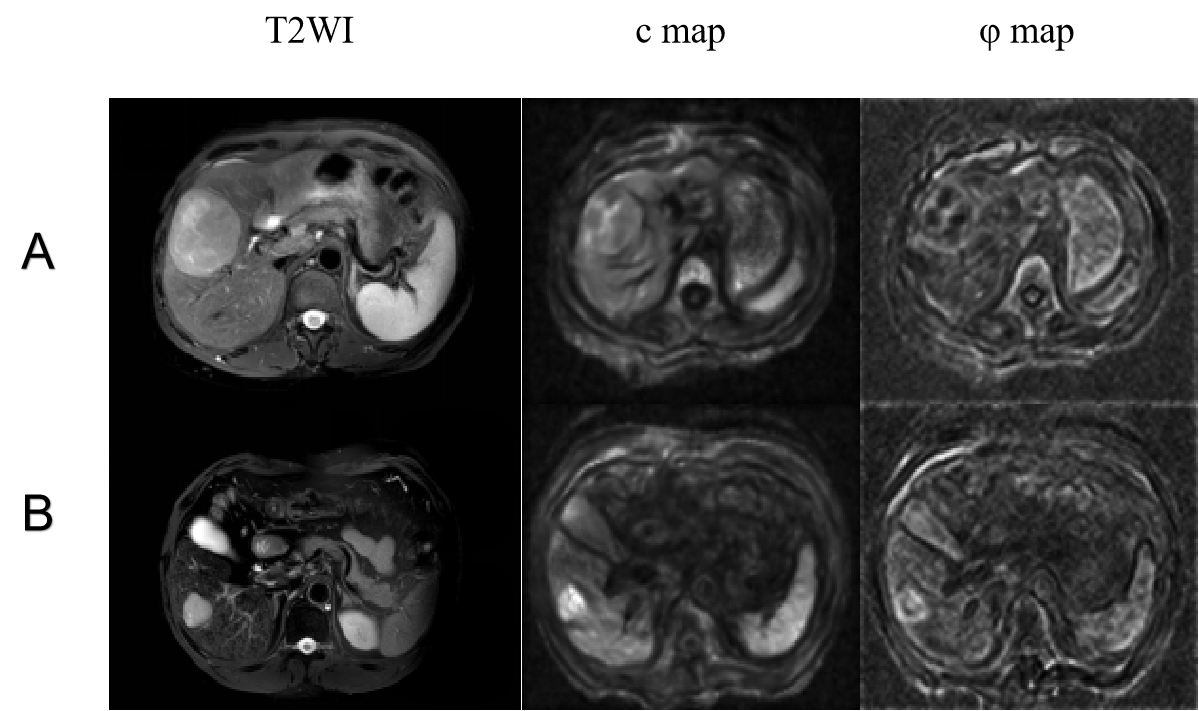

Figure 2: Representative axial T2-weighted images; c and φ maps of tumors in a non-cirrhotic (fibrosis stage F3; TSC = 1.56) (A) and a cirrhotic patient (fibrosis stage F4; TSC = 1.69) (B).